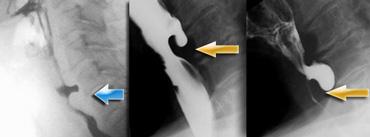

Trường hợp bên trái là một ca bệnh đặc biệt, nhưng minh họa rõ nét sự khó khăn đôi khi gặp phải trong việc xác định nguyên nhân gây bất đối xứng.

Ở hình ngoài cùng bên trái, bất đối xứng được thấy trên nghiên cứu huỳnh quang (mũi tên xanh lá).

Có vẻ như có gì đó trong xoang lê bên phải.

Trên hình ảnh đối quang kép bên phải, xoang lê bình thường (mũi tên xanh lá), nhưng ở mức thung lũng nắp thanh quản bên phải thấy một tổn thương dạng thùy (mũi tên vàng).

Ở mức cao hơn, thấy một vết lõm nhẵn của hầu miệng (mũi tên xanh dương).

Khối u dạng thùy ở mức thung lũng nắp thanh quản được xác định là phần còn lại của amidan lưỡi, đây là phát hiện thường gặp và đôi khi khó phân biệt với ung thư đáy lưỡi.

Vết lõm của hầu miệng do động mạch cảnh trong bị dài ra (mũi tên xanh dương). So sánh với vị trí của động mạch cảnh bên trái

Hình ảnh CT cho thấy vết lõm nhẵn của hầu miệng bên phải là do động mạch cảnh trong bị dài ra gây nên.

Đây quả thực là một trường hợp hiếm gặp, trong đó trên nghiên cứu huỳnh quang ban đầu nghi ngờ có khối u ở xoang lê.

Cuối cùng phát hiện một tổn thương trong hầu miệng và một tổn thương chèn ép thành từ bên ngoài ở mức cao hơn.

Do các tổn thương này, thuốc cản quang đi qua hạ hầu bất đối xứng, giả tạo hình ảnh tổn thương ở xoang lê.